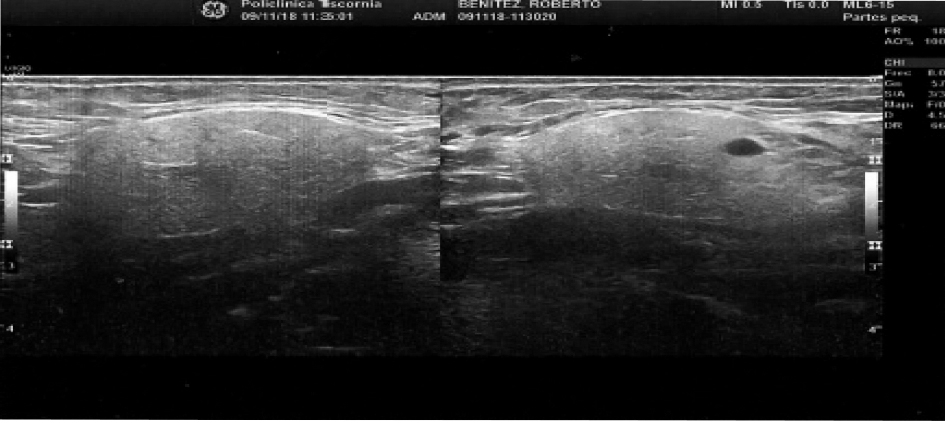

Se solicita ecografía que demuestra glándulas salivales agrandadas sin alteraciones en el parénquima a destacar. Relata que unas pocas horas después del estudio contrastado, al comer, nota incremento del dolor y deformación en el cuello. Se efectúa tratamiento de hemodiálisis habitual y, durante el mismo, se administra hidrocortisona 500 mg por vía EV, AINE´s por vía oral. Una hora más tarde, refiere atenuación del dolor y se observa disminución generalizada del edema en forma simétrica. Se le indican AINE´s y antibacterianos. En la tercera semana muestra resolución parcial con tumefacción de las glándulas parótidas y submaxilar izquierda.(Imagines 3, 4 y 5)